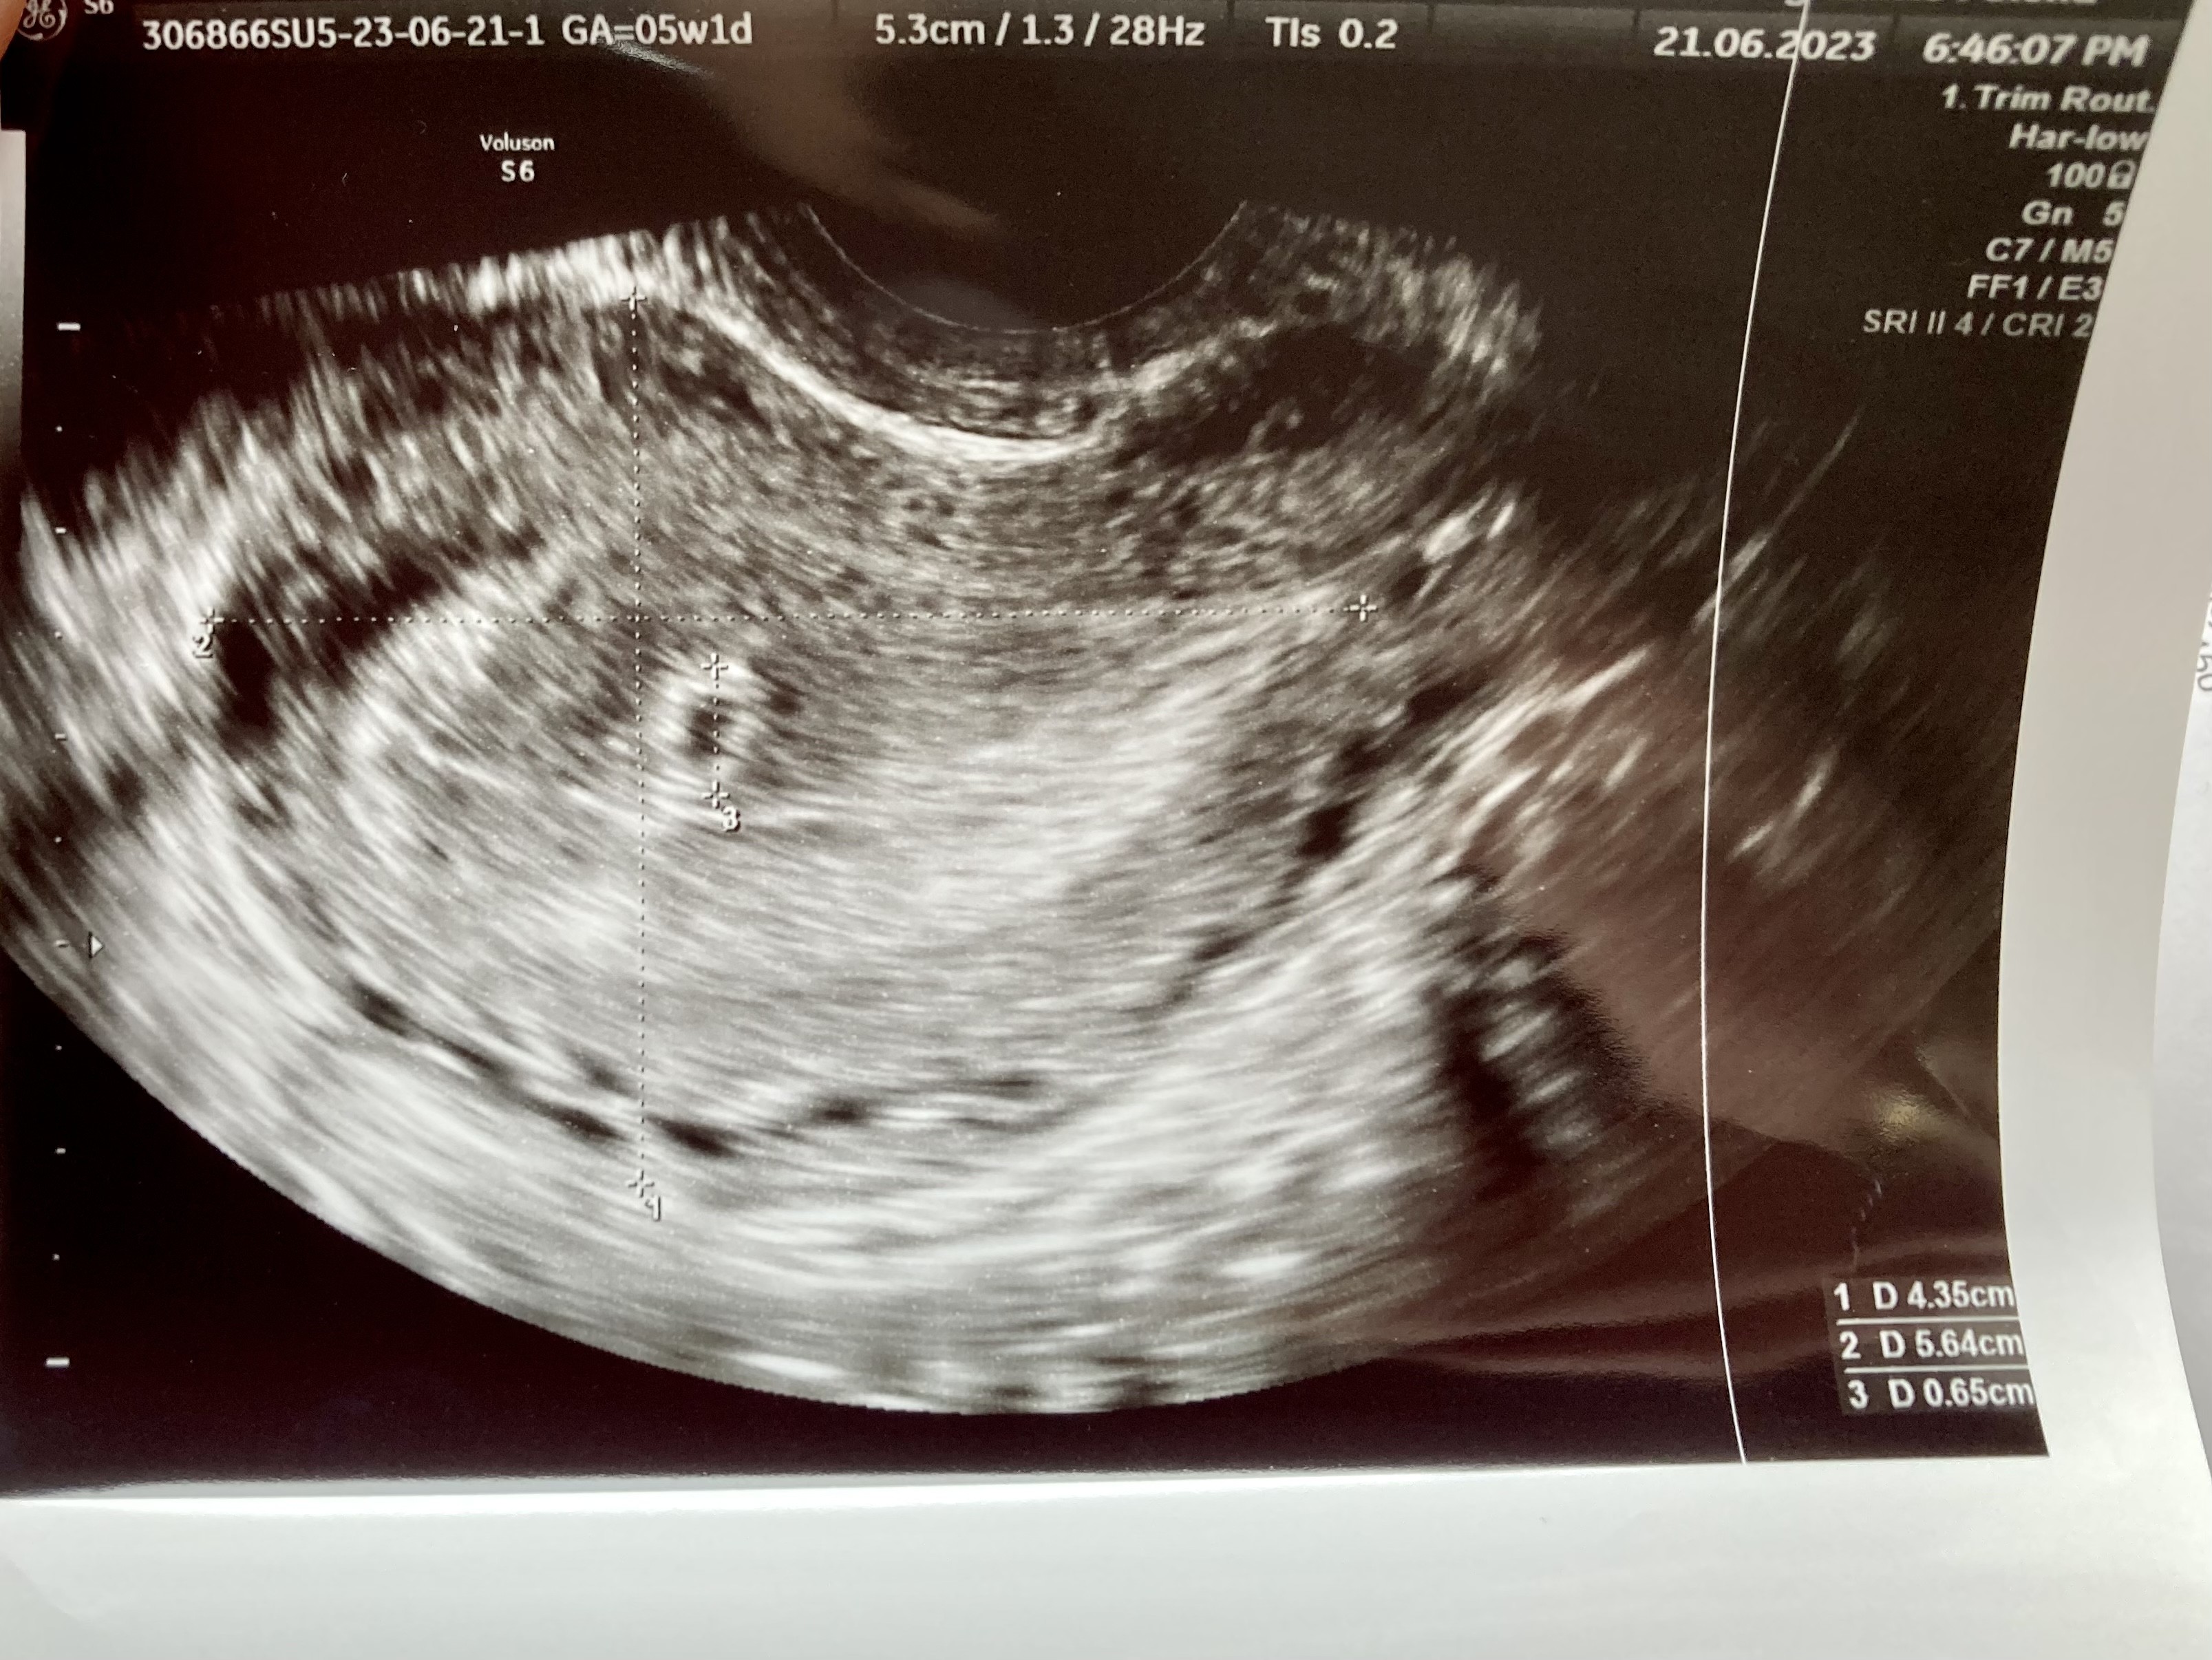

W Medicoverze , z męża pracy mam pakiet. Badania z krwi też mam w pakiecie![]()